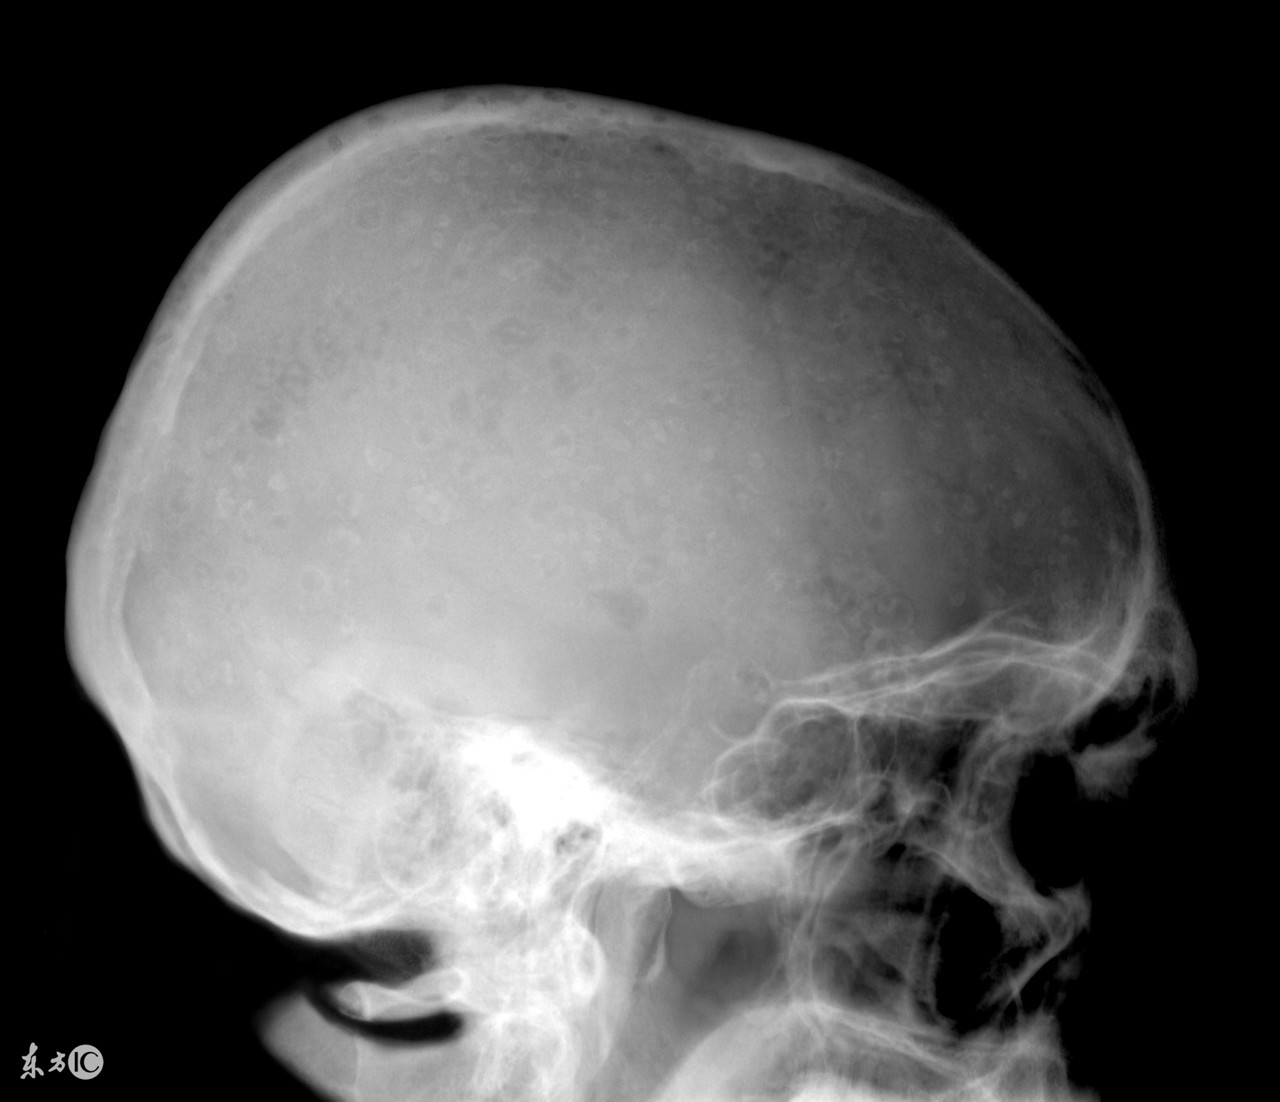

越来越多的人受到了多发性骨髓瘤的困扰,我们大家都知道,患了多发性骨髓瘤会对我们的身体和心理健康造成很大的危害,因此发现患病之后一定要积极的进行治疗,而且多发性骨髓瘤的治疗也是有一定难度的,那么,多发性骨髓瘤大概需要花费多少钱?

治疗多发性骨髓瘤费用其实和患者的病情严重程度有着密切的关联,而且较为严重的时候还会引起消化系统、心血管系统、运动系统等多器官病变,严重可导致死亡。所以想要了解治疗多发性骨髓瘤疾病究竟需要多少钱是需要根据患者病情的严重程度才能确定,因为对于不同程度的治疗多发性骨髓瘤的方法不同,相对应的费用也是不一样的,所以当患上这种疾病之后,一定要第一时间到医院接受治疗,避免病情恶化而导致治疗难度增大,费用增多。